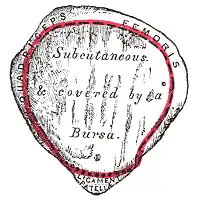

Kniescheibe

Die Kniescheibe ist dreieckig und an ihrer Vorderfläche etwas nach außen gewölbt. Sie ist als Sesambein in die Ansatzsehne des vierköpfigen Oberschenkelmuskels (Musculus quadriceps femoris) eingelagert, der sie von oben kommend einbettet. Von ihrer unteren Spitze (Apex patellae) entspringen die Fasern des Kniescheibenbandes (Ligamentum patellae). Auf der Hinterseite der Kniescheibe (Facies articularis patellaris) befindet sich ein First, der die Gelenkflächen in zwei Facetten unterteilt. Ihre Knorpelschicht ist etwa sechs Millimeter dick.

Bei gebeugtem Knie liegt die Kniescheibe fest in der Furche kurz oberhalb des Gelenkspaltes zwischen Oberschenkelknochen und Schienbein, bei gestrecktem Bein weiter oberhalb. Deshalb lässt sie sich zwar bei Streckstellung und entspannter Muskulatur ein wenig nach rechts und links verschieben, jedoch nicht in Beugestellung.

Hauptaufgabe der Kniescheibe ist die Verlängerung des Hebelarms und somit des Drehmoments des Quadrizeps, da sie den Abstand seiner Kraftwirkungslinie vom Bewegungszentrum des Kniegelenks erhöht. Zudem dient sie der Führung der Sehne und verringert den Widerstand der Gleitbewegung der Sehne über den Knochen.

Schleimbeutel

Um Schäden an den über das Gelenk ziehenden Sehnen vorzubeugen, besitzt das Kniegelenk an besonderen Reibungspunkten oberhalb, vor und unterhalb des Kniegelenkes Schleimbeutel (Bursae), von denen einige eine Verbindung zum Gelenkraum besitzen (Bursa oder Recessus suprapatellaris[12] und Bursa infrapatellaris). Die Bursa infrapatellaris schiebt sich zwischen Kniescheibenband und Schienbein. Ein Schleimbeutel befindet sich hinten in der Gelenkhöhle unter der Ansatzsehne des halbhäutigen Muskels (Musculus semimembranosus) (Bursa musculi semimembranosi). Zwei weitere liegen unter den Ursprungssehnen des zweiköpfigen Wadenmuskels (Musculus gastrocnemius) (Bursa subtendinea musculi gastrocnemii lateralis und Bursa subtendinea musculi gastrocnemii medialis).

Zwei Schleimbeutel besitzen keine Verbindung zum Gelenkraum und sind somit in sich abgeschlossen. Der eine liegt unter der Haut vor der Kniescheibe (Bursa subcutanea prepatellaris), der andere liegt zwischen dem Kniescheibenband und der äußeren Schicht der Gelenkkapsel (Bursa infrapatellaris profunda).